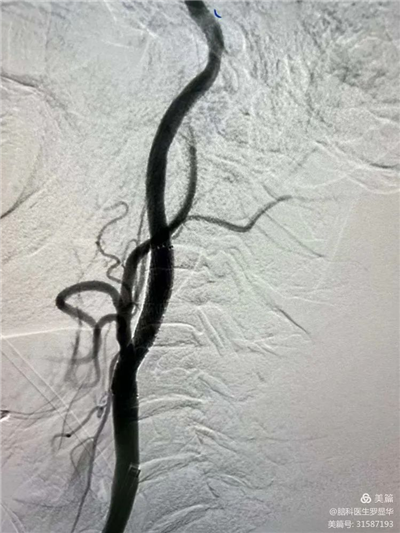

李東波副院長團(tuán)隊正在為患者行頸動脈支架植入術(shù)

手術(shù)過程:指引導(dǎo)管到位

手術(shù)過程:球囊擴張后,protege支架到位

術(shù)后造影示狹窄解除